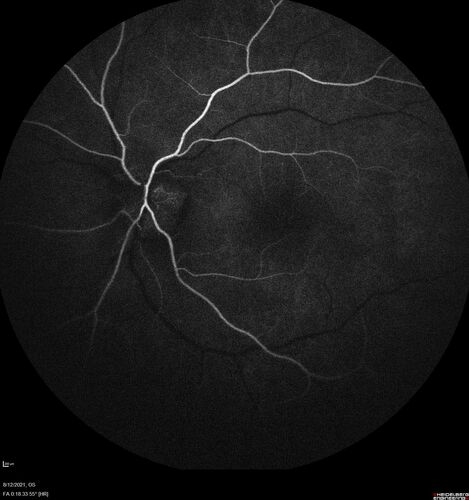

Neuroretinitis left eye - recovered with no therapy - possible B pertussis

57 year old female The patient has had blurred vision in the left eye and there is a haze across the top of the vision.  This started about 2 weeks ago.  The right eye is OK.  She has sleep apnea and uses the machine.  The left eye is becoming more and more painful for the last two weeks.  The pain is like a stabbing in the eye that comes and goes.  She also has some pain on eye movement.  The patient has been going to Moffit for possible reconstructive surgery for the lymphedema.

PMHx – Sleep apnea, Breast Cancer, Adult lymphedema,

Meds: Gabapentin

VA OD: Dcc20/25-1

VA OS: Dcc20/100-2

AC quiet OU.  1 + NS cataract OU

IOP: TP: OD:15 OS:17